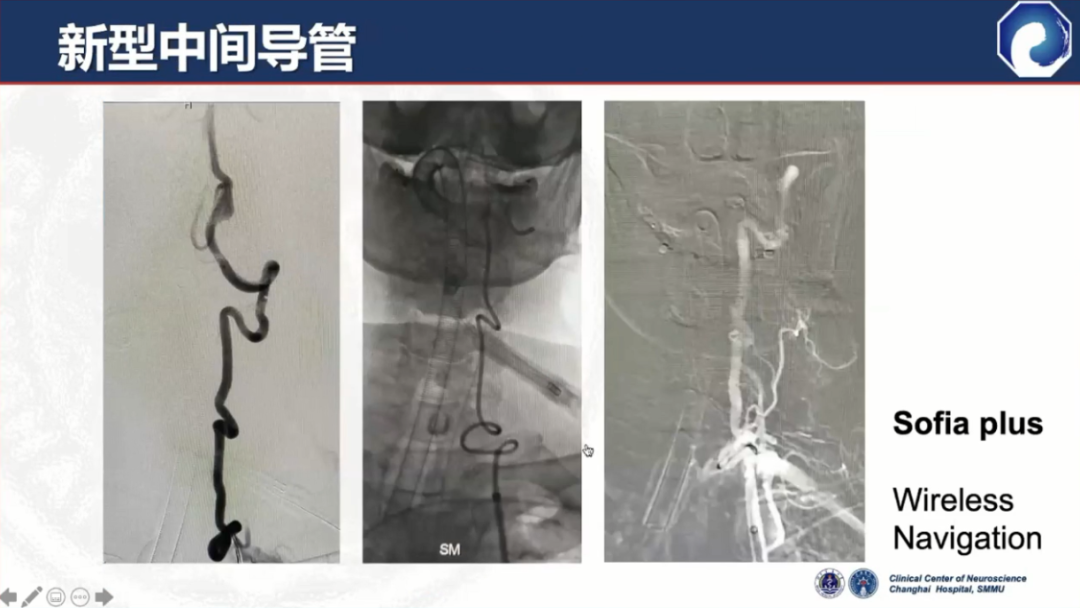

以Navien为代表的第二代中间导管诞生,通过性和到位能力有了显著提升